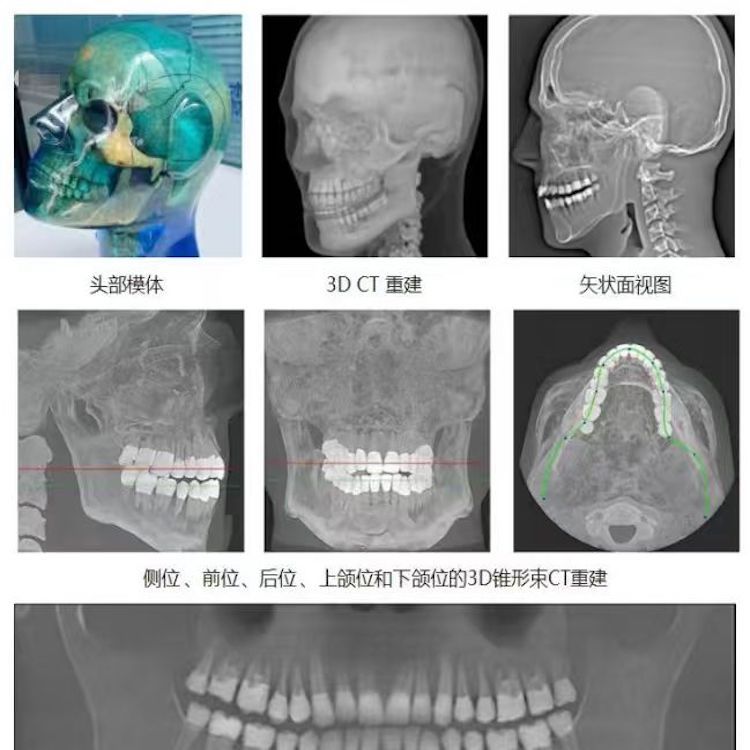

頭部模體是頭部診斷放射學(xué)的參考標(biāo)準(zhǔn),該模體旨在協(xié)助技術(shù)和臨床人員,在大多數(shù)需要精細(xì)解剖細(xì)節(jié)的放射學(xué)程序中選擇、監(jiān)測(cè)、培訓(xùn)和驗(yàn)證掃描參數(shù)。 模體為研究人員、臨床醫(yī)生和技術(shù)人員提供了一致性的工具。它非常適合確定最佳系統(tǒng)設(shè)置、調(diào)試新設(shè)備、監(jiān)測(cè)系統(tǒng)性能和培訓(xùn)牙科X射線、全景X射線、CT和錐束CT程序。 這個(gè)模體包括一個(gè)可調(diào)節(jié)的支架,用于在錐束 CT 或全景X射線系統(tǒng)中定位。模體的下頜略微張開,前牙垂直排列,以復(fù)制正確的咬合引導(dǎo)定位 。 請(qǐng)注意,實(shí)際咬合引導(dǎo)無法在這個(gè)產(chǎn)品中定位。 頭部模體是由專有組織等效材料制成的。由組織模擬樹脂制成,這些樹脂模擬X射線對(duì)人體的衰減特性,適用于CT和治療能量范圍(50keV-25MeV)。 模體在大小和結(jié)構(gòu)上都近似于平均男性頭部 。該模體包括詳細(xì)的3D擬人化解剖結(jié)構(gòu), 包括大腦、骨骼、喉、氣管、鼻竇、鼻腔和牙齒。骨骼包括皮質(zhì)和骨小梁的分離。牙齒包括明顯的牙本質(zhì)、牙釉質(zhì)和包括神經(jīng)的牙根結(jié)構(gòu)。鼻竇完全張開。

頭部模體特點(diǎn) 1. 詳細(xì)的解剖特征; 2. 確定法蘭克福平面以確保正確對(duì)齊; 3. 50 keV 至 25 Mev 的組織等效值; 4. 具有六個(gè)自由度的定位支架; 5. 包括泡沫內(nèi)襯手提箱; 6. 12個(gè)月保修。

功能和應(yīng)用 1. X射線 ,全景X射線 ,CT和錐束CT系統(tǒng); 2. 學(xué)習(xí)如何正確定位頭部以獲得最佳圖像; 3. 測(cè)試重建技術(shù)和算法 ,用于植入物規(guī)劃和頜面部重建; 4. 在實(shí)施新設(shè)備和新技術(shù)期間培訓(xùn)并評(píng)估人員; 5. 驗(yàn)證圖像質(zhì)量的一致性。